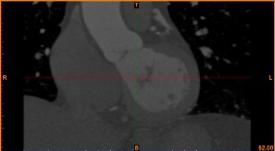

病例描述:

病人患冠心病,堵塞處較多,決定采用搭橋治療。

首先通過病人的心臟冠脈造影CT數據,獲取病人的心臟冠脈三維模型。

病人的冠脈造影CT數據                                              提取出的冠脈三維數據

其次在對應的病灶位置進行一定的細節修改,或改變其形狀或改變顏色以便于突出顯示病灶位置。

模型細節修改